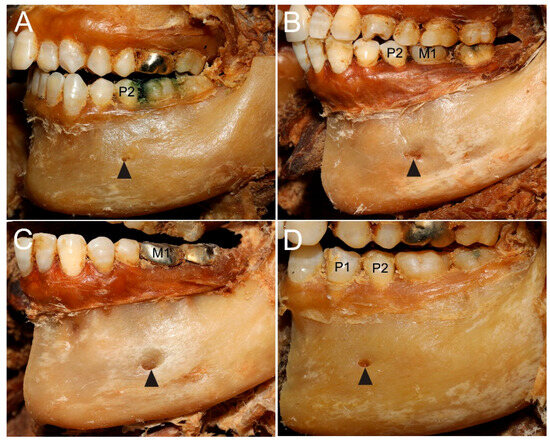

3.1. Morphology and Location of the MF